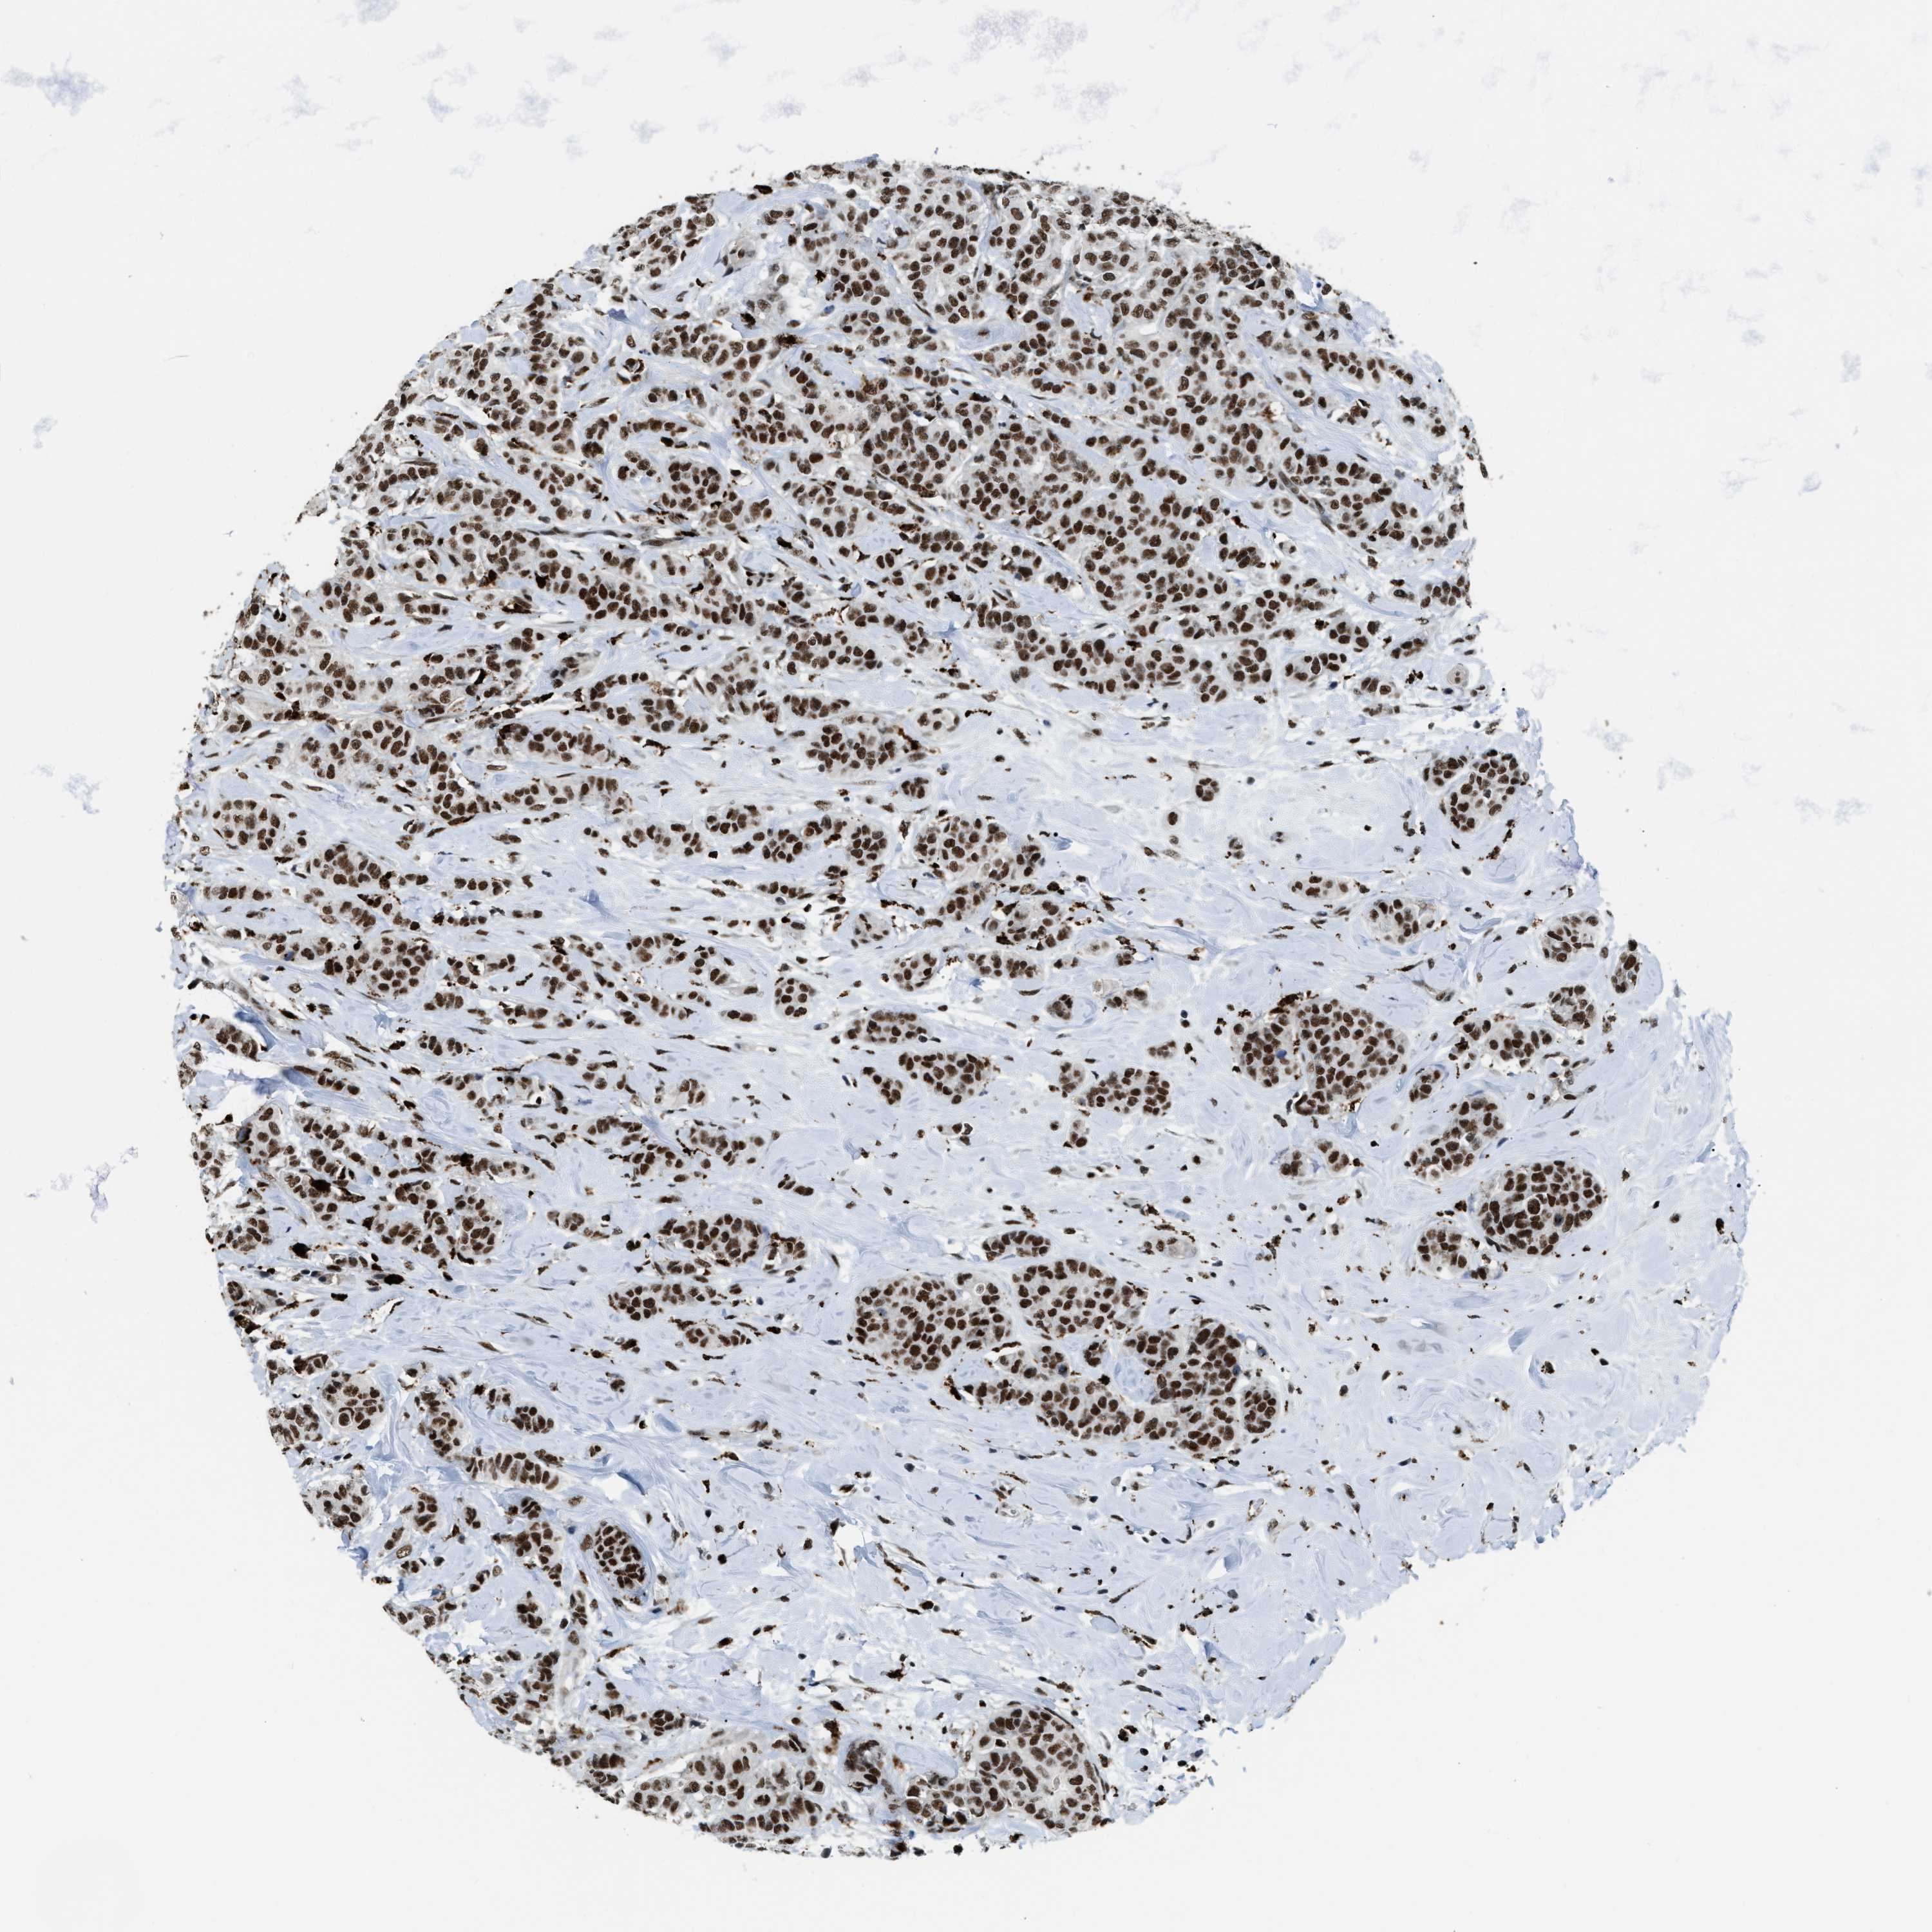

CANCER BREAST CANCER Show tissue menu

BRCA TCGA BRCA VALIDATION PROTEIN EXPRESSION

ANTIBODIES

AND

VALIDATION